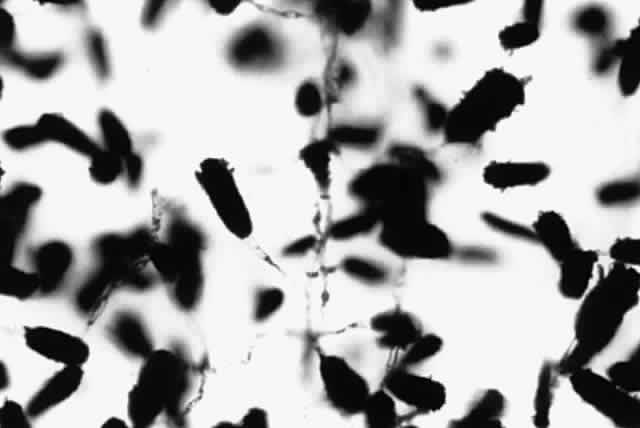

NOCARDIA SPECIES.

Growth occurs on Sabourauddextrose agar without antibiotics, Lowenstein-Jensen medium, and Middlebrook 7H11 agar and matures within 7 to 9 days. Colonies on Sabouraud dextrose agar are white to orange, raised, irregular or smooth (Fig. 9). Microscopically on tap water agar are seen thin, delicate, branching, beaded filaments that fragment into bacillary or coccoid forms (Fig. 10). They are gram positive and may be partially acid fast. There are three major pathogens to humans: N. asteroides, N. brasiliensis, and N. otitidiscaviarum.

Fig. 9. Colony of Nocardia asteroides on Sabouraud dextrose agar.

Fig. 10. Growth of Nocardia asteroides on tap water agar showing branching aerial mycelia (X 40).